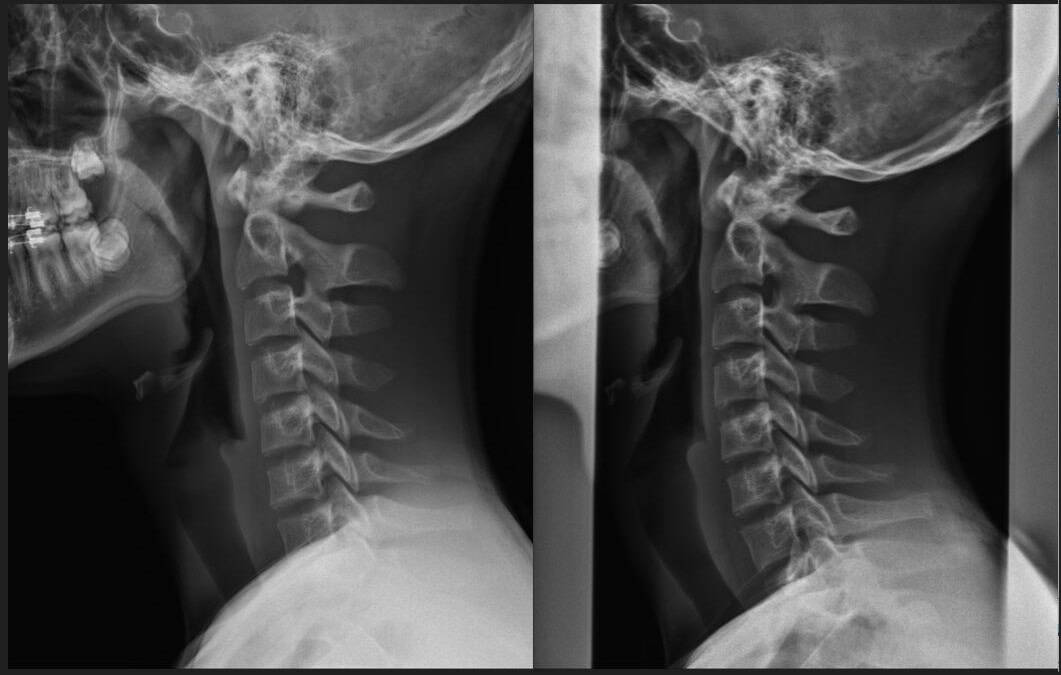

Pre & Post Scan